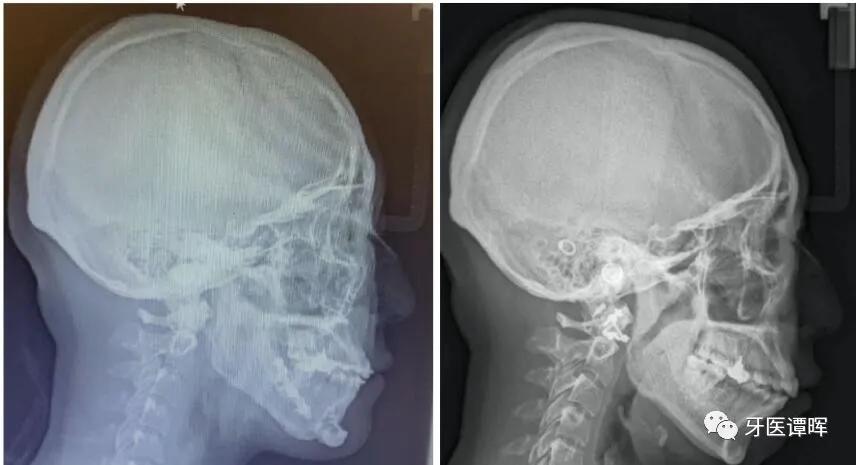

拍 片

一般的龅牙矫正和地包天矫正都是要拍头颅侧位片,用于头影测量,得出相应的数据,就知道暴牙突出的根源所在,知道是牙齿的原因还是骨骼的原因,决定是否则拔牙的重要依据。

其它情况下也可能要拍片,医生根据实际情况而定。